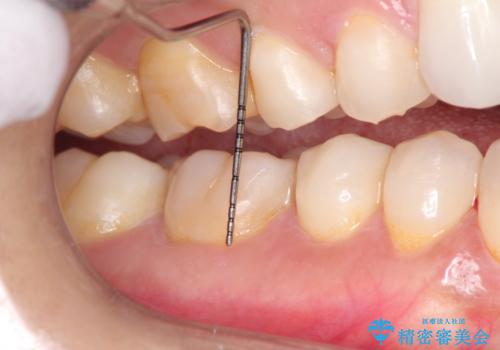

- 昔に受けた矯正治療がきっかけで歯肉が下がってしまった事を主訴として来院された患者様です。

結合組織移植術を行う方法を提案しましたが、傷口が口蓋にもできるのが嫌だとのことで、代替案としてバイオマテリアルを併用した根面被覆術を計画致しました。

治療対象部位は右下4,5,6番の3本です。